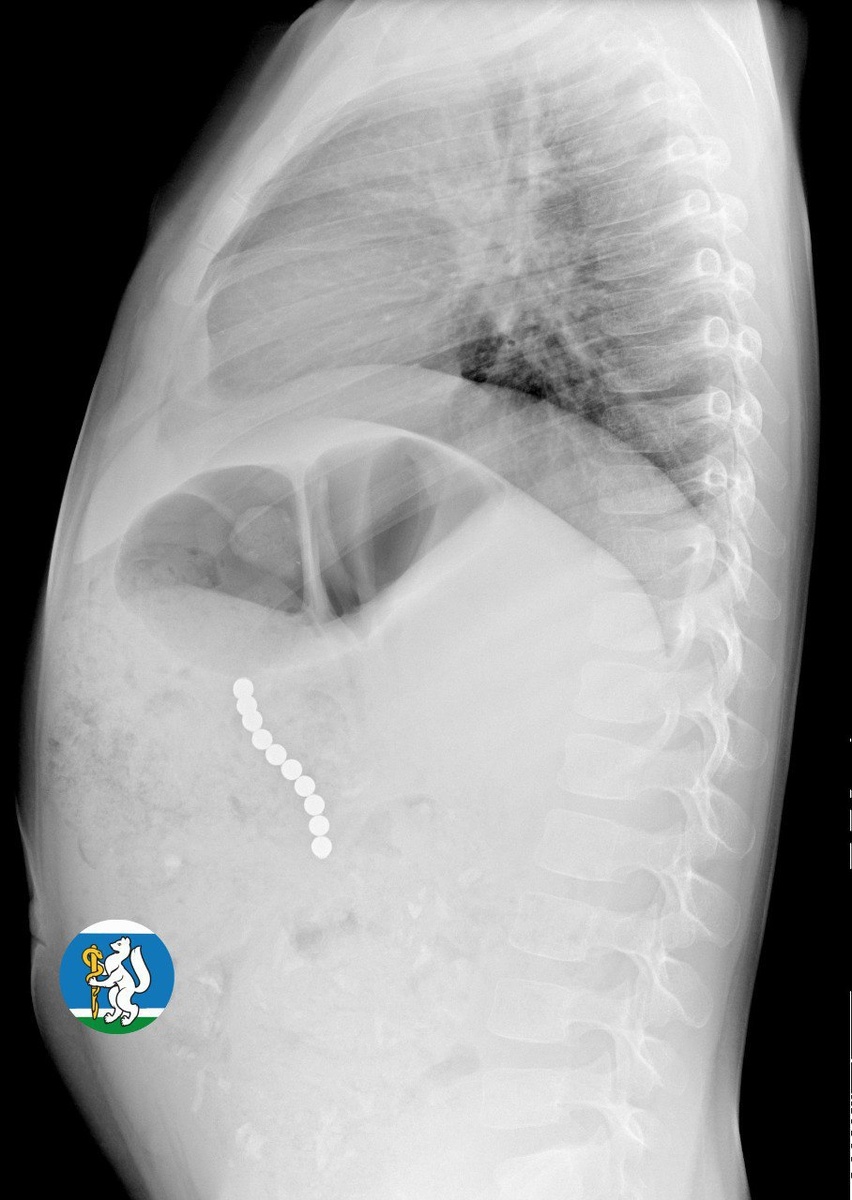

Екатеринбургские врачи спасли девочку, проглотившую 10 магнитных шариков

Врачи ДГКБ № 9 Екатеринбурга спасли маленькую Ульяну, которая проглотила десяток магнитных шариков.

Как сообщили в пресс-службе областного минздрава, шарики соединились друг с другом через стенки внутренних органов и повредили их. Цепочка из опасных предметов длиной 5 сантиметров могла привести к перитониту и гибели ребенка. К счастью, родители вовремя обратились к участковому педиатру, который направил девочку на рентген. Увидев на снимке цепочку из магнитных шариков, медики направили Ульяну в детскую городскую клиническую больницу № 9, где ее прооперировали.

«Для минимизации риска осложнений удаление инородных тел было проведено интраоперационно. В ходе вмешательства дежурная бригада врачей извлекла 10 магнитных шариков, цепочка которых в длину составила 5 сантиметров», – рассказал детский хирург ДГКБ № 9 Андрей Чукреев.